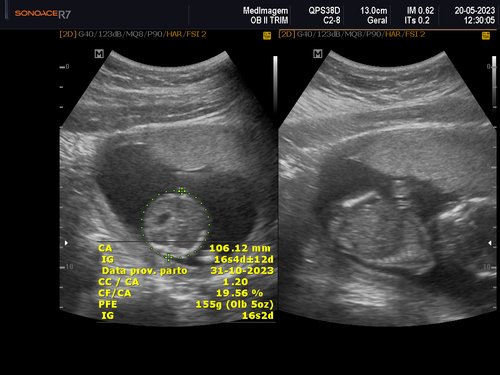

Eu tenho 27 anos estou grávida de 4 meses essa é a minha quarta gestação as minhas três últimas gestações eu perdi os bebês nunca consegui levar a gravidez adiante, eu quero muito conseguir levar essa, MINHA GRAVIDEZ É DE ALTO RISCO.

Uma amiga me deu a ideia de fazer uma vaquinha online, para conseguir fazer o tratamento no particular e o parto também, com ajuda de alguns amigos consegui arrecadar um valor e começar o tratamento no particular tive uma consulta com uma médica maravilhosa doutora Rochelle Hygino que na primeira consulta já me encaminhou para internação e para cirurgia, precisei fazer uma cerclagem no útero que é costurar o útero para segurar o bebê.